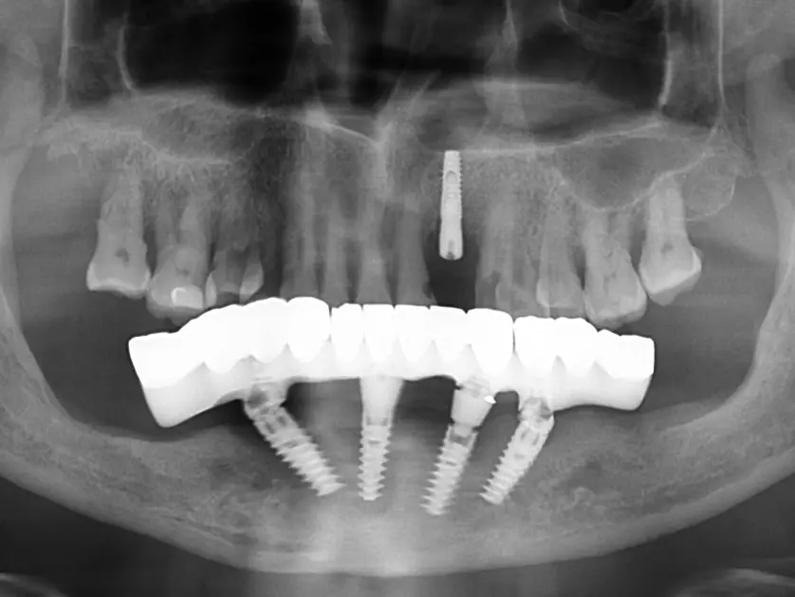

贵阳君雅京恬口腔种牙贵吗,单颗种植牙6704元至1

贵阳君雅京恬口腔种植牙的价格因患者口腔状况和选择方案的不同而呈现较大差异,单颗种植牙价格在6704元至19645元之间,...